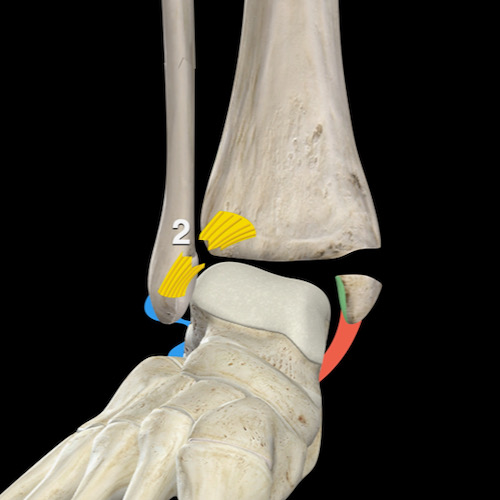

Bước 3 – Liệu đây có phải là Weber C / PER không?

Khi X-quang cổ chân không cho thấy gãy xương rõ ràng như Weber A hoặc B, câu hỏi đặt ra là: liệu đây có phải là gãy xương Weber C không?

Vì đường gãy xương mác trong Weber C thường không hiển thị trên X-quang cổ chân, đây có thể là một câu hỏi khó trả lời.

Chúng ta sẽ phải tìm kiếm các dấu hiệu bổ sung để dẫn đến câu trả lời đúng và giúp chúng ta quyết định có cần chụp thêm hình ảnh hay không.

Vì đường gãy xương mác đã ở giai đoạn 3, chúng ta muốn tìm kiếm:

- Giai đoạn 1 là tổn thương phía trong (medial), nơi mọi thứ bắt đầu. Bất kỳ cơn đau hoặc phù nề phần mềm ở phía trong đều có thể là dấu hiệu đầu tiên cho thấy chúng ta đang đối mặt với gãy xương Weber C.

- Giai đoạn 2 là tổn thương khớp chày mác xa (syndesmosis) phía trước, thường không nhìn thấy được, trừ khi có gãy xương Tillaux.

- Giai đoạn 4 là tổn thương khớp chày mác xa phía sau, đôi khi không thể nhìn thấy, nhưng sẽ bị nghi ngờ nếu có sự giãn rộng của khớp cổ chân hoặc khi có mảnh avulsion của mắt cá sau (malleolus tertius) như được thấy trong hình minh họa.

Cơ chế chấn thương Weber C

Cơ chế của Weber C là kết quả của tư thế bàn chân sấp (pronation) kết hợp với lực xoay ngoài (exorotation) tác động lên bàn chân, đó là lý do tại sao Lauge-Hansen gọi nó là sấp – xoay ngoài (pronation exorotation – PER).

Các giai đoạn bao gồm:

- Do tư thế sấp, có một lực căng rất lớn tác động lên các dây chằng bên trong (medial collateral), và đó là nơi tổn thương bắt đầu với hoặc là đứt dây chằng hoặc là gãy avulsion mắt cá trong (giai đoạn 1).

- Khi lực xoay ngoài tiếp tục, khớp chày mác xa phía trước sẽ bị đứt (giai đoạn 2).

- Do tư thế sấp của bàn chân, các dây chằng ở phía ngoài đều không có lực căng. Khi bàn chân tiếp tục xoay ngoài, đầu dưới xương mác đi theo chuyển động xoay ngoài này, trong khi đầu trên xương mác được giữ cố định tại khớp chày mác gần, tạo ra một đường gãy xoắn ở vị trí nào đó phía trên mức khớp chày mác xa (giai đoạn 3).

- Và cuối cùng ở giai đoạn 4, sẽ xảy ra đứt khớp chày mác xa phía sau hoặc gãy avulsion mắt cá sau (giai đoạn 4).

Trên mặt phẳng trục (axial), có thể thấy tổn thương bắt đầu ở phía trong do tư thế sấp của bàn chân và tiến triển theo chiều kim đồng hồ qua phía trước, phía ngoài đến phía sau.

Và cũng giống như trong Weber B, có thể xảy ra tổn thương khớp chày mác xa phía trước, xương mác và cuối cùng là khớp chày mác xa phía sau.